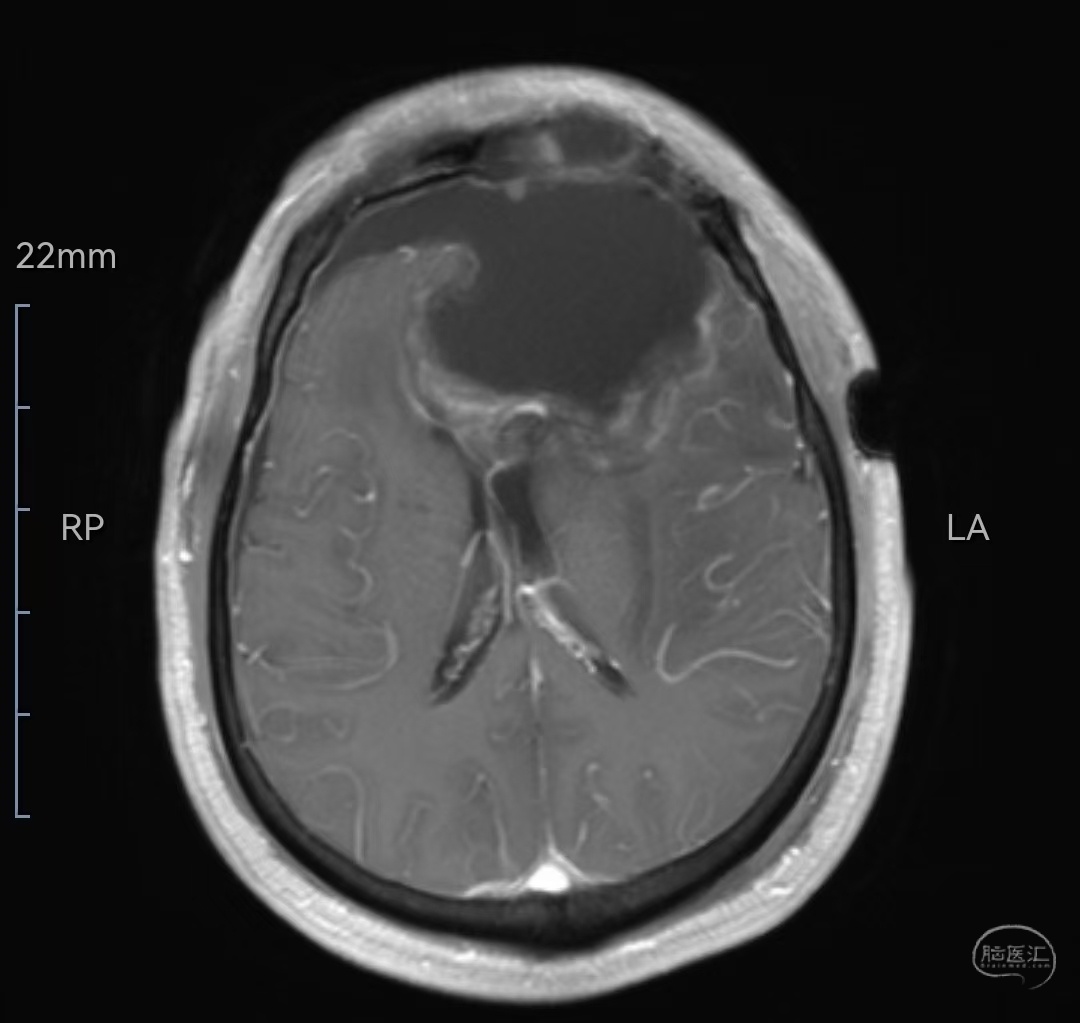

MRIT1相轴位示肿瘤等信号,位于双侧额叶,左侧为主,已侵犯至胼胝体嘴、膝部及左侧颞岛叶

MRI增强轴位示肿瘤明显强化,位于双侧额叶,左侧为主,已侵犯至胼胝体嘴、膝部及左侧颞岛叶。肿瘤最大直径7厘米